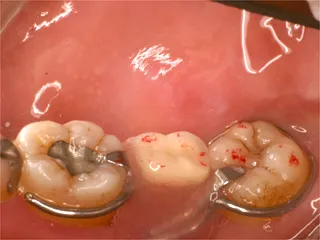

保険のブリッジ